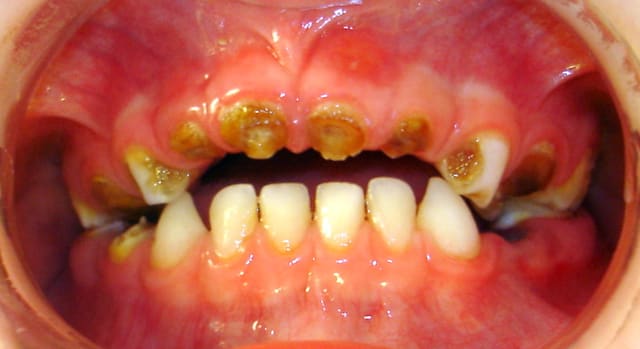

Voici Tony : il vient d'avoir 4 ans. Il a été élevé avec un biberon pour s'endormir, puis plus grand avec du soda à volonté, grignotage non contrôlé.

Cela fait plusieurs mois qu'il se plaint de douleurs et des moqueries à l'école sur son état bucco-dentaire.

L'examen clinique indique l'avulsion de toutes les dents temporaires hormis le bloc 73 à 83.

Malgré son jeune âge, l'enfant est très réceptif à ce qu'on lui dit et coopératif. La maman me semble au 1er abord "inconsciente", presque "fautive" : mais après discussion, elle n'avait juste pas considéré les conséquences. Elle se montre réceptive et ne ratera aucun RDV. Au second RDV, les conseils d'hygiène locale et alimentaire semblent bien assimilés.